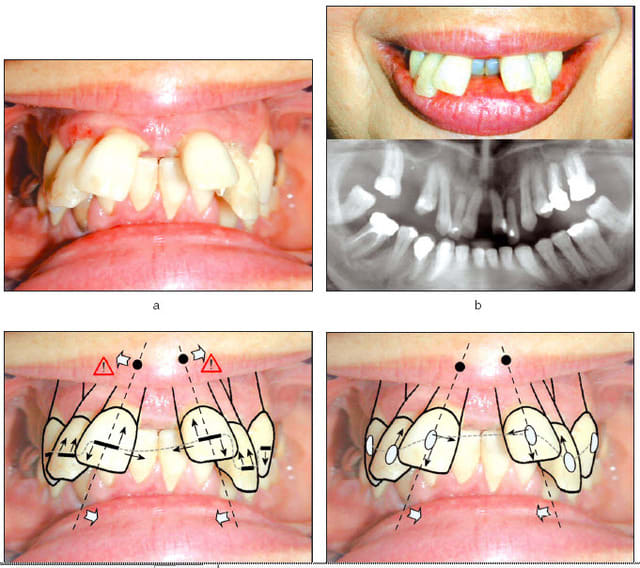

Deux images du dispositif.

La connectique s'appelle "CTO" dans notre classification. Ici, c'est une "libellule" modifiée.

"Cortical" : application directe sur la corticale.

"TMA" : Titane-Molybdène-Alloy (nature du fil)

"O" : terminaison en forme de "O", à différencier du "8" ou du "8" tunnel.

En fait, quand on regarde les radios de profil avant et après, on constate que l’ingression des incisives s’est accompagné également d’un recul des apex en palatin. Ceci peut paraître étonnant car le fil était rond et quand on veut faire du torque on utilise un fil de section carrée ou rectangulaire.

Comment expliquer ce résultat ?

Personnellement, je pense que c’est dû à la conjonction de deux éléments :

1 - l’utilisation des attaches minimalistes « danchimon » ( cf l'article de l’Orthodontie Française de septembre 2009 ), les seules qui permettent aux dents de se mouvoir en toute liberté dans la direction souhaitée grâce à un glissement incomparable du fil dans leur lumière et une étroitesse qui ne génère pas de mouvements parasites latéraux aux apex comme toutes les autres attaches actuellement sur le marché, autoligaturants style « Damon » compris (voir l’effet d’un fil avec les deux types d’attaches sur le schéma du bas de la première des photos ci-jointes. Il n’aurait pas été possible de rentrer cette 22 sortie de l’os autrement qu’avec des danchimons car il était nécessaire que l’incisive retrouve elle-même son alvéole - Notez que « danchimon » est désormais le nom officiel de ces attaches, on ne parle plus de « danchamon » en dehors d'eugenol..).

2 - La pression musculaire de l’orbiculaire des lèvres au niveau sous-nasal, avec ses imbrications avec le transverse du nez qui forment un couloir musculaire efficace que va suivre les apex.